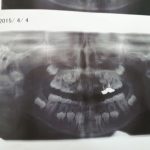

《とり》の矯正に行きました。最近は経過観察です。乳歯がまだあるので紹介状をもらい今度抜歯する事になりました。噛み合わせが深かったのも治りました。

生えるスペースのない歯が他の歯の根を溶かしてしまうそうなので防止できてよかったです。